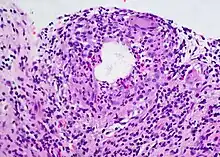

Diagnosis

A chalazion or meibomian cyst can sometimes be mistaken for a stye.

Differential diagnosis

- Sebaceous gland adenoma

- Sebaceous gland carcinoma

- Sarcoid granuloma

- Foreign body granuloma